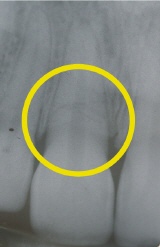

Wurzelbruch nach Sportunfall

Das Röntgenbild zeigt die Bruchlinie in der Miitte des gelben Kreises als schwaze dünne Linie horizontal verlaufend.